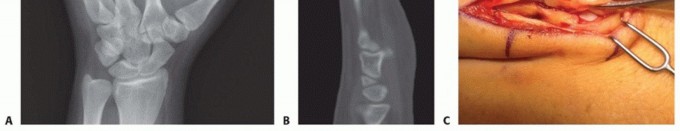

FIG 6 • Dorsal approach to the MP joint of an index finger. Extensor tendon beneath top retractor. Capsule grabbed by pickup forceps. Articular cartilage seen deep to capsule.

DORSAL APPROACH FOR FIXATION

TECH FIG 4 • (continued) G,H. Motion at 6 weeks after surgery. The periosteum is elevated at the fracture site to assist with assessment of fracture reduction. As much of the interosseous muscle is left attached to the metacarpal as feasible to preserve blood supply to the bone.The fracture is reduced and provisionally stabilized with reduction clamps (TECH FIG 4D).